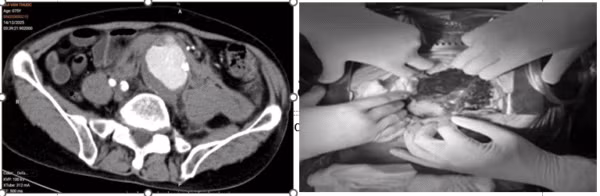

Với tinh thần khẩn trương, quyết liệt cùng năng lực chuyên môn vững vàng, kinh nghiệm dày dạn, ê-kíp đã nhanh chóng thực hiện phẫu thuật và kiểm soát chảy máu, ổn định huyết động; thay đoạn động mạch chủ, đưa người bệnh trở về từ “lằn ranh sinh tử”.

chu-bung-1.jpg

Hình ảnh người bệnh được phẫu thuật thay đoạn động mạch chủ bụng - Ảnh BVCC